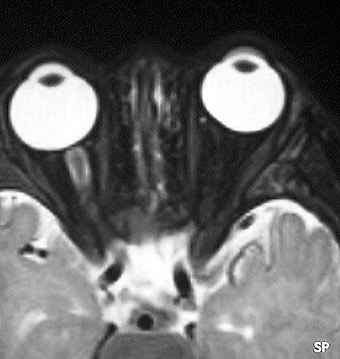

乳児にできた視神経膠腫です(左側の写真)。腫瘍が眼窩内にとどまっていて左の目はすでに失明していましたから,腫瘍を手術で全部とりました(右側の写真)。このような手術は腫瘍が反対側の視神経にいかないようにするために視神経交差のところで切り離すので,開頭手術が必要です。眼球も残っていますし再発はありません。